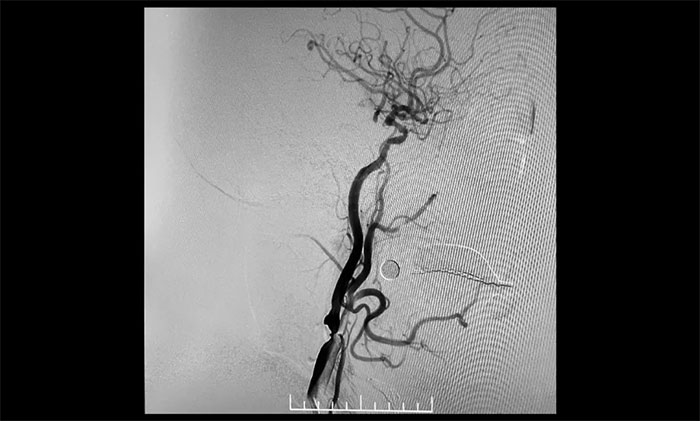

患者為老年男性,因言語不利,伴右側肢體活動不利入院。外院行頭顱CT檢查:雙側腦室旁及基底節(jié)區(qū)腔隙灶。入院后,頭顱MRI平掃+DWI+MRA提示,腦干、雙側小腦及雙側大腦半球多發(fā)腔梗、缺血灶;MRA:腦動脈硬化,左側頸內(nèi)動脈不完全閉塞,右側頸內(nèi)動脈C3-C6段、右側大腦中動脈M2段多發(fā)狹窄。“主動脈弓+全腦動脈造影”提示:右頸內(nèi)動脈起始段重度狹窄,左頸內(nèi)動脈起始段重度狹窄,串聯(lián)左頸內(nèi)動脈巖骨段中度狹窄,左頸內(nèi)動脈眼動脈段閉塞。

▲ 右頸內(nèi)動脈起始段重度狹窄